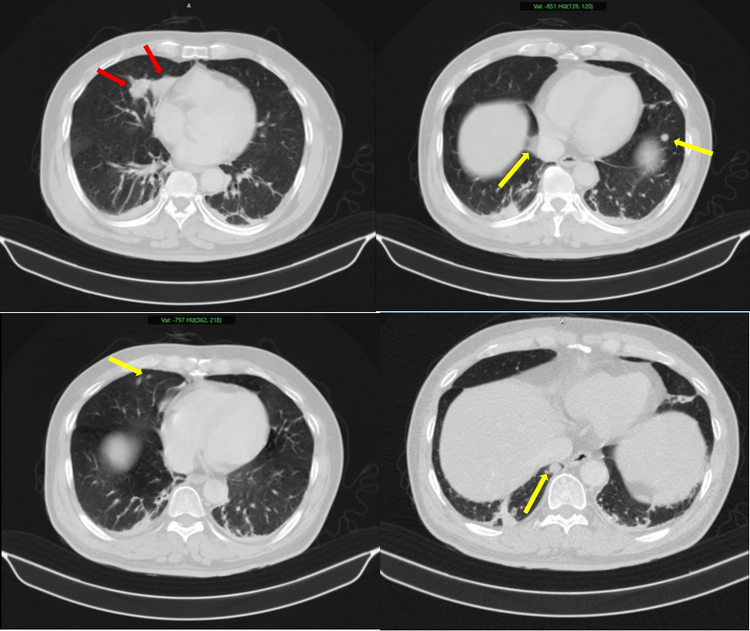

ung-thu-phoi-1.png

Hình ảnh 2 khối u bờ đa cung ở nhu mô thùy giữa phổi phải, dính vào màng phổi trung thất (mũi tên đỏ) kèm nhiều nốt đặc nhỏ rải rác nhu mô phổi hai bên (mũi tên vàng) gợi ý tổn thương thứ phát - Ảnh BVCC